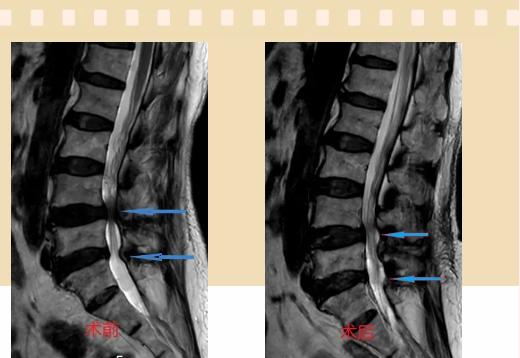

近日,漯河市骨科醫(yī)院(漯河醫(yī)專二附院、漯河市立醫(yī)院)智能微創(chuàng)骨科(骨十科)收治了一位72歲女性患者,主要癥狀是下肢麻木,不能走遠(yuǎn)路,行走約100米就需要蹲下休息,生活質(zhì)量很低。

入院后李鵬副主任醫(yī)師為其進(jìn)行了詳細(xì)的查體,完善了術(shù)前的檢查,明確診斷為:腰椎管狹窄癥(L4/5、L5/S1),病人合并2型糖尿病,請內(nèi)分泌科會(huì)診,穩(wěn)定血糖后,麻醉科會(huì)診病人,排除手術(shù)禁忌,李鵬為病人制定了手術(shù)方案:單側(cè)入路雙側(cè)減壓(ULBD)。

手術(shù)采用三個(gè)微創(chuàng)小切口,兩個(gè)節(jié)段減壓手術(shù)時(shí)間2.5小時(shí),出血50ml。術(shù)后2天腰圍保護(hù)下床活動(dòng),術(shù)后5天順利出院。

傳統(tǒng)腰椎管狹窄癥的手術(shù)治療,往往需要切開減壓,同時(shí)需要內(nèi)固定融合術(shù),創(chuàng)傷很大,同時(shí)可能需要輸血,臥床時(shí)間較長,病人合并糖尿病,感染風(fēng)險(xiǎn)也高,而本次采用的UBE-ULBD手術(shù)切口更?。悠饋砑s3cm,如果是單節(jié)段狹窄只需要不到2cm切口)、創(chuàng)傷更小,術(shù)后恢復(fù)較快,可以更早地恢復(fù)正?;顒?dòng)。

此外,手術(shù)保留了病變節(jié)段的穩(wěn)定性,是一種微創(chuàng)的椎管減壓手術(shù),能通過切除部分椎板、關(guān)節(jié)突關(guān)節(jié)、黃韌帶來解除神經(jīng)根和硬膜囊的壓迫,不需要額外行腰椎內(nèi)固定術(shù),不需要螺釘及融合器的植入,病人術(shù)后腰椎的活動(dòng)度不受影響。(盧   闖  劉   旭   袁錦鈺)